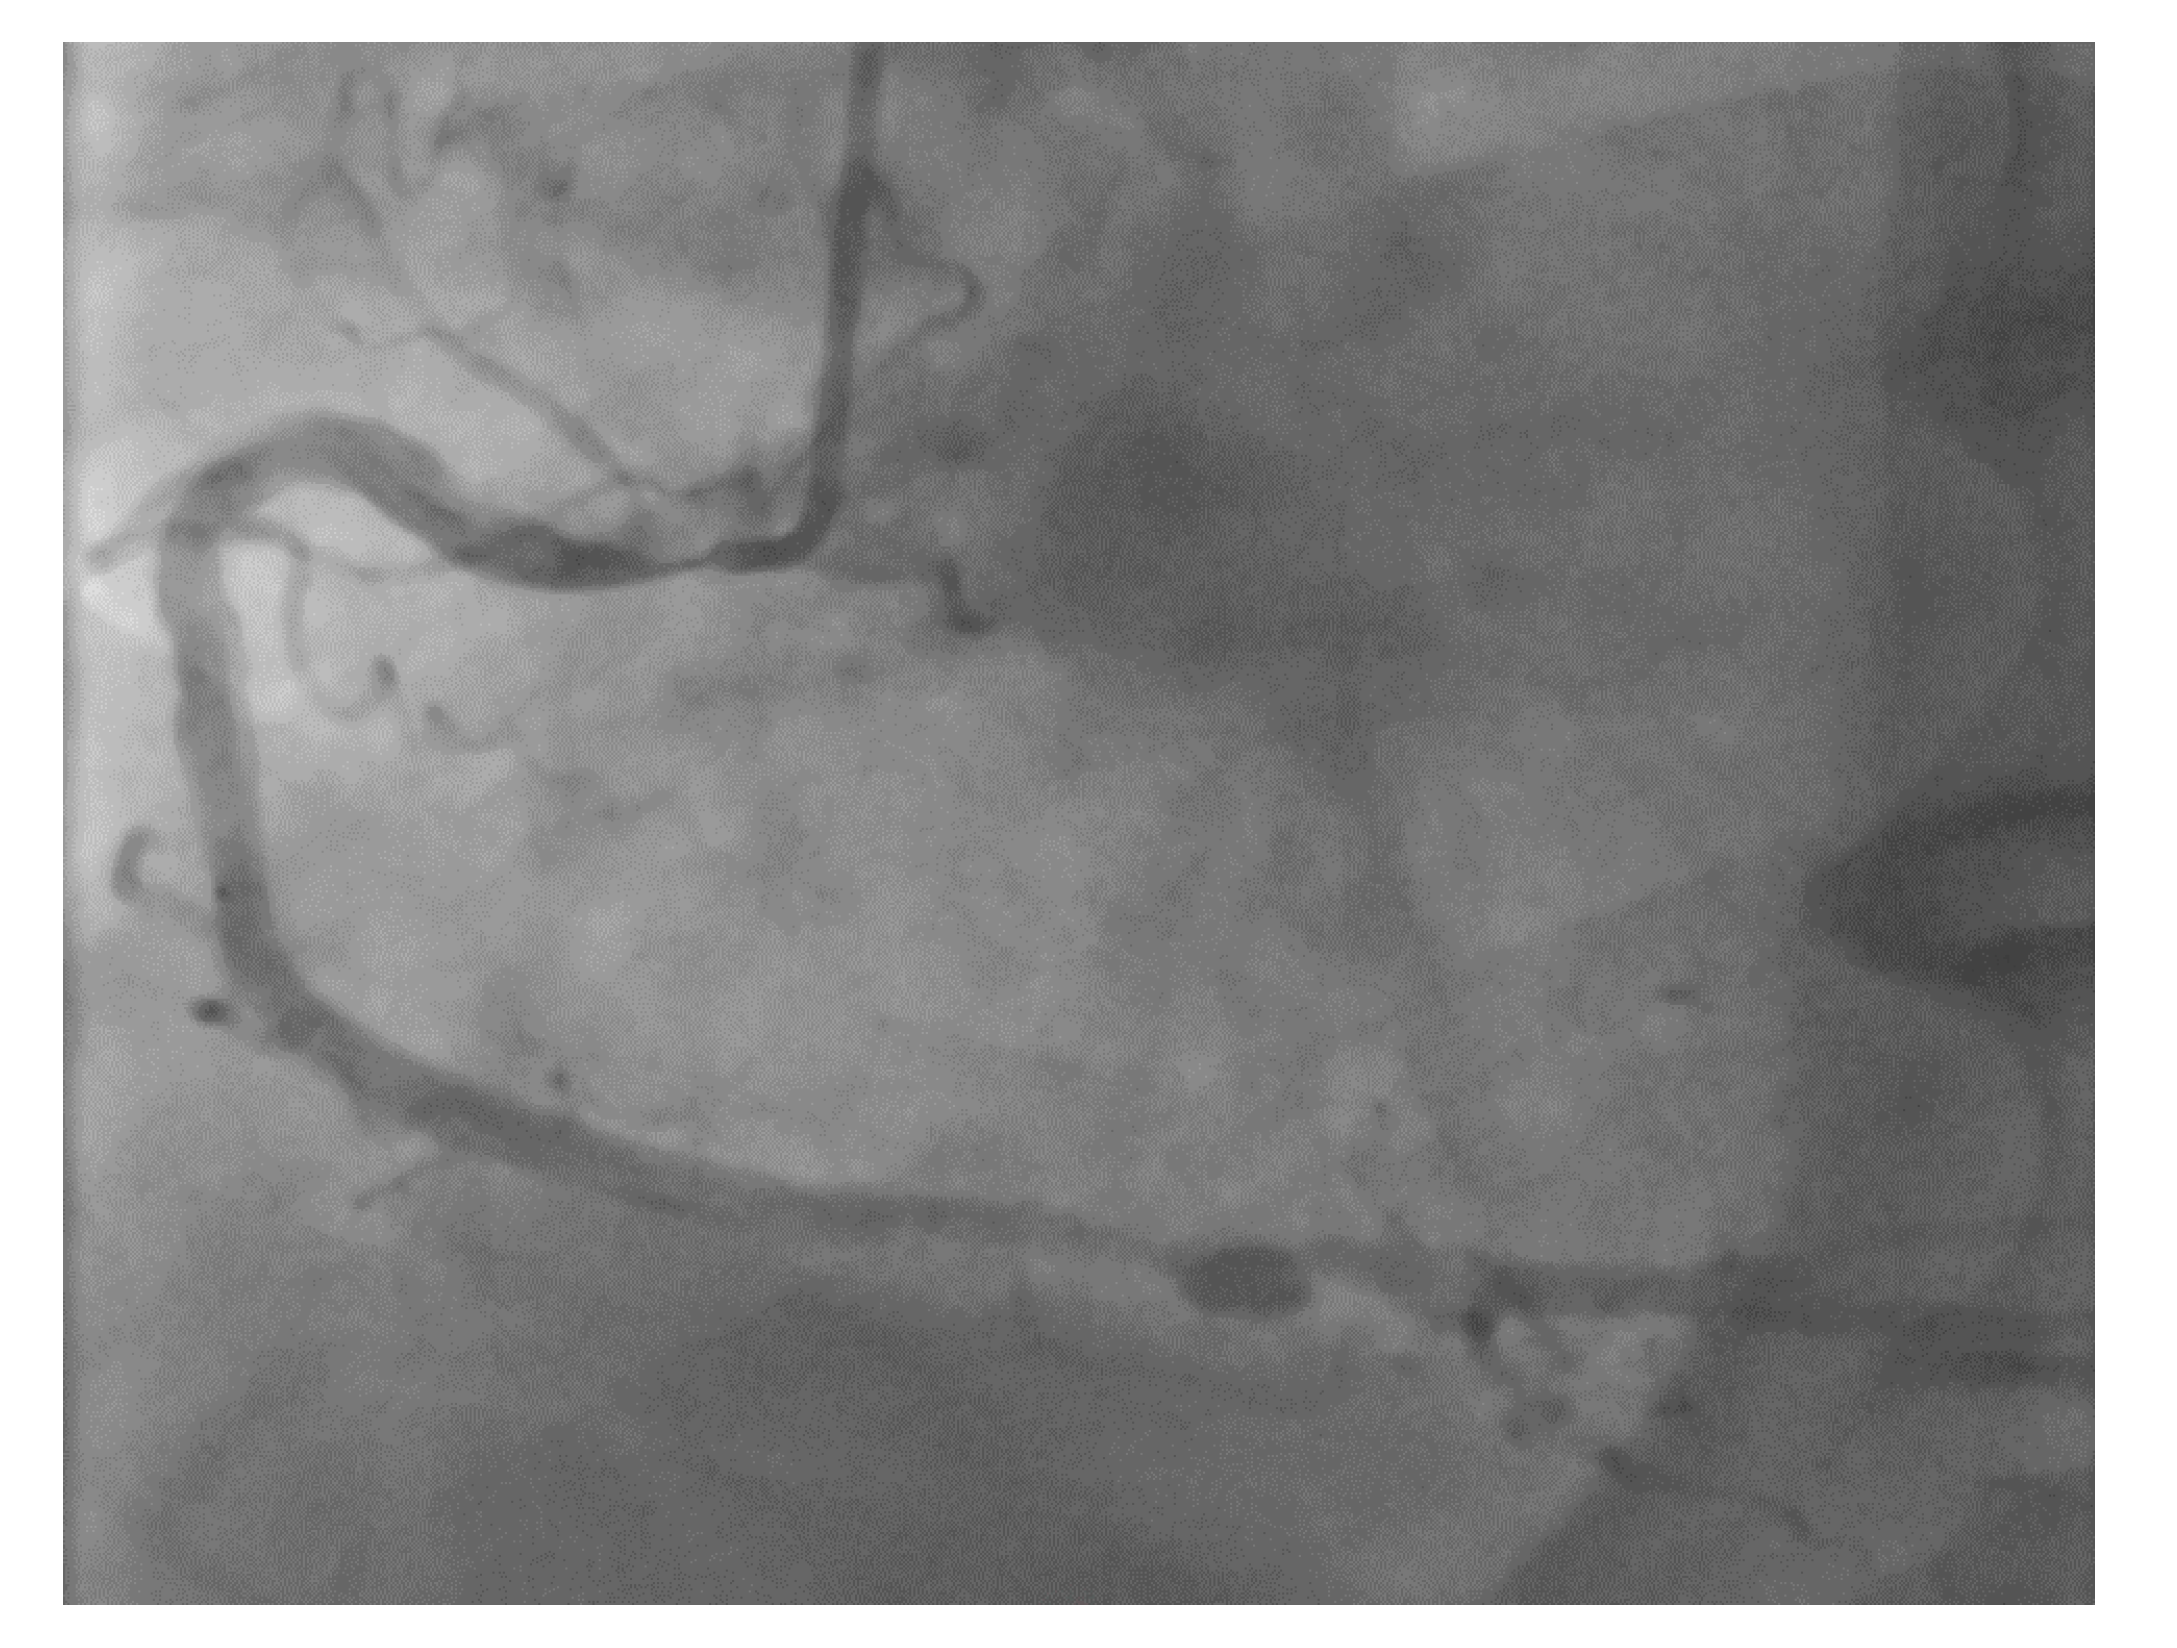

However, an ideal robotic intervention is one where the operator obtains access and performs initial guide placement manually, and is then able to complete the entire intervention from the cockpit without having to re-scrub, even briefly, to perform some portion manually. An example of an excellent case for robotic PCI is a two vessel PCI of the left anterior descending and circumflex arteries, where one guide shape and a single guidewire is used for both vessels, and where significant radiation exposure or a prolonged time in lead are both avoided. Figure 2 shows an example of an ideal robotic PCI case.

Figure 2. Example of an ideal case for robotic PCI. These images are from a 72 year-old with unstable angina referred to our hospital for intervention. Diagnostic catheterization showed moderate disease in the LAD (A) but with fractional flow reserve of 0.65 and severe disease of the LCX (B) with chronic occlusion of the RCA. The LAD and LCX were both treated successfully robotically with post-stent images shown in (C).